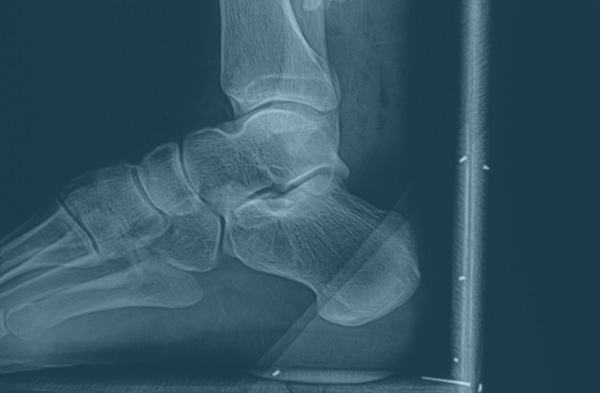

Live Life to its fullest, reclaim your active lifestyle with our personalized Orthopedic Care

I employ advanced orthopedics to revitalize mobility & empower limitless living.

Comprehensive Orthopedic Care

We meticulously craft personalized orthopedic strategies, tailored to each patient's unique healthcare needs, ensuring comprehensive and precision-driven care.